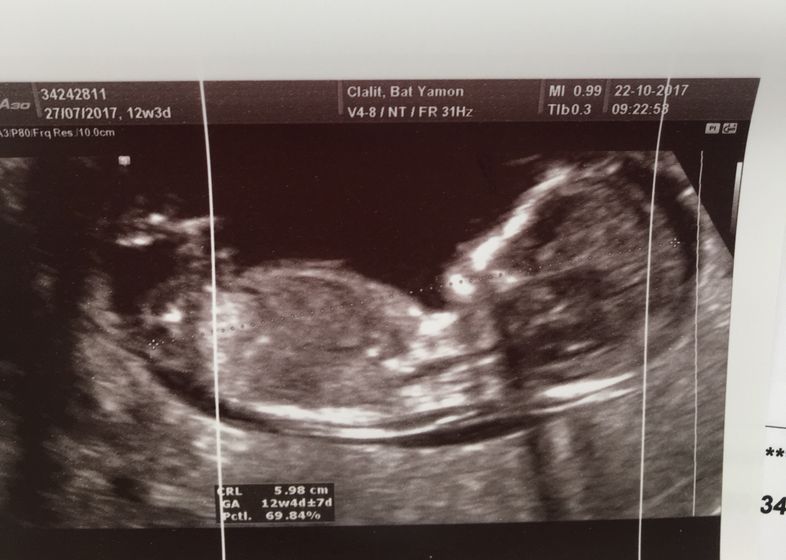

Вот и мы сегодня прошли наш первый скрининг) волновалась жуть… по УЗИ вроде всё хорошо ? врач был не русскоязычный, поэтому я толком ничего не спрашивала) единственное он уверенно сказал, что у нас мальчик и всё хорошо!!!) ктр 6см. срок 12.4 на один денёк опережаем месячные)) Риски по возврату-1:1249, а по результатам УЗИ 1:8327. Результаты анализа крови, будут аж через 2 недели. Кто делал скрининг на моем сроке? Какие у вас результаты?

Сразу видно, что мальчишка ?

Я тоже ещё до того как врач сказал пол, подумала походу мальчик, что то я там мельком увидела?

Нет, там все одинаково на этих сроках, половые бугорки одинакового размера, только у мальчишек "торчком", как на Ваших первых фотографий, поэтому сомнений нет! Поздравляю!